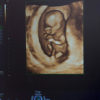

Il giorno del trasferimento dell’embrione è il più emozionante e importante per ogni coppia sottoposta alla procedura di fecondazione in vitro. Questo è il momento in cui tutte le speranze e i sogni si uniscono.Read more